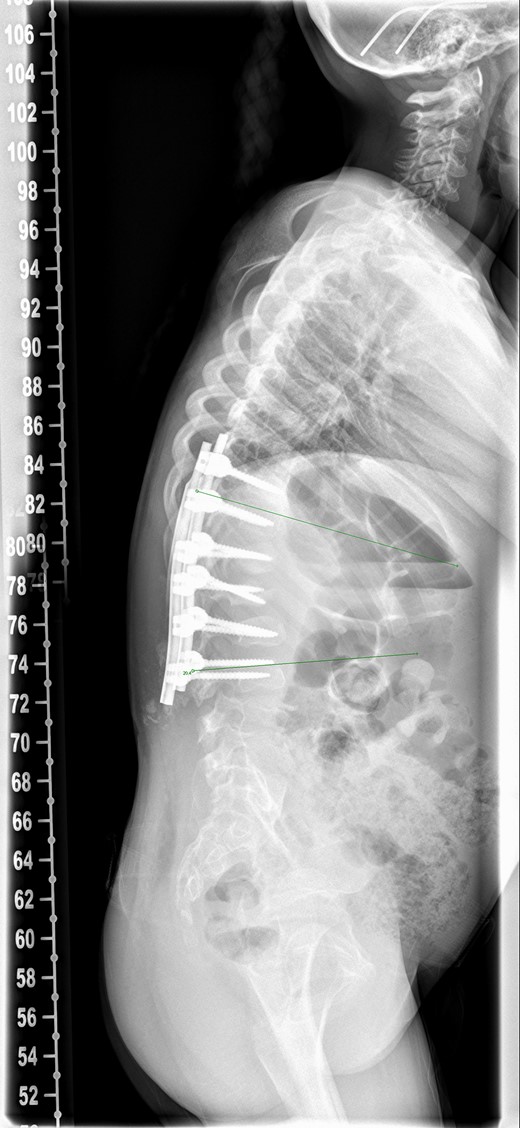

An 8-year-old girl with Mucopolysaccharidosis 1 and high lumbar kyphosis (Fig. 1) was admitted for posterior spinal fusion. Surgery was performed in prone position with multimodality spinal cord monitoring using a posterior midline approach. Spinal fixation was done with pedicle screws from T10 to L3 vertebrae. Spinal osteotomies were performed and kyphosis was corrected. It is the senior surgeon’s preference to augment fusion with i-Factor in order to promote early fusion in this patient group. Two 50 mm i-FactorTM bone graft Flex FR strips were cut along their length, one half was placed medial to the implants over the lamina and the other half placed lateral to the implants in posterolateral gutter. Allograft was placed on top of the strips. Wound was closed in layers leaving behind a drain over the fascia.

There was serous discharge with flakes of i-Factor in the drain postoperatively. Wound drain was removed on the second day and postoperative radiograph (Fig. 2) was satisfactory. Patient was discharged with a dry wound on the fifth day. Patient reattended hospital on seventh day with serous discharge from the drain site. There was no sign of infection and the wound was covered with a PICOTM dressing (Smith and Nephew), a negative pressure wound therapy system. At Day 10 the primary wound was healed, but serous fluid containing i-Factor flakes noted from the drain site. Patient was not started on antibiotics as there was no sign of infection and blood markers were normal. Wound was kept covered with a dressing and the discharge stopped.